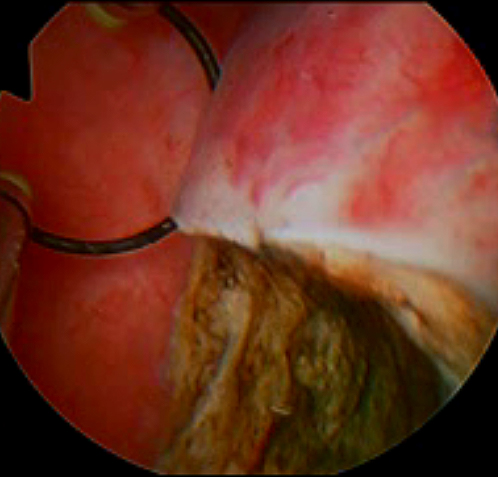

The fibroid pseudocapsule is composed of a rich neurovascular network in neurofibers similar to the neurovascular bundle surrounding the prostate.Continue Reading

The “cold loop” hysteroscopic myomectomy was presented at the beginning of the nineties for the first time at the NationalContinue Reading